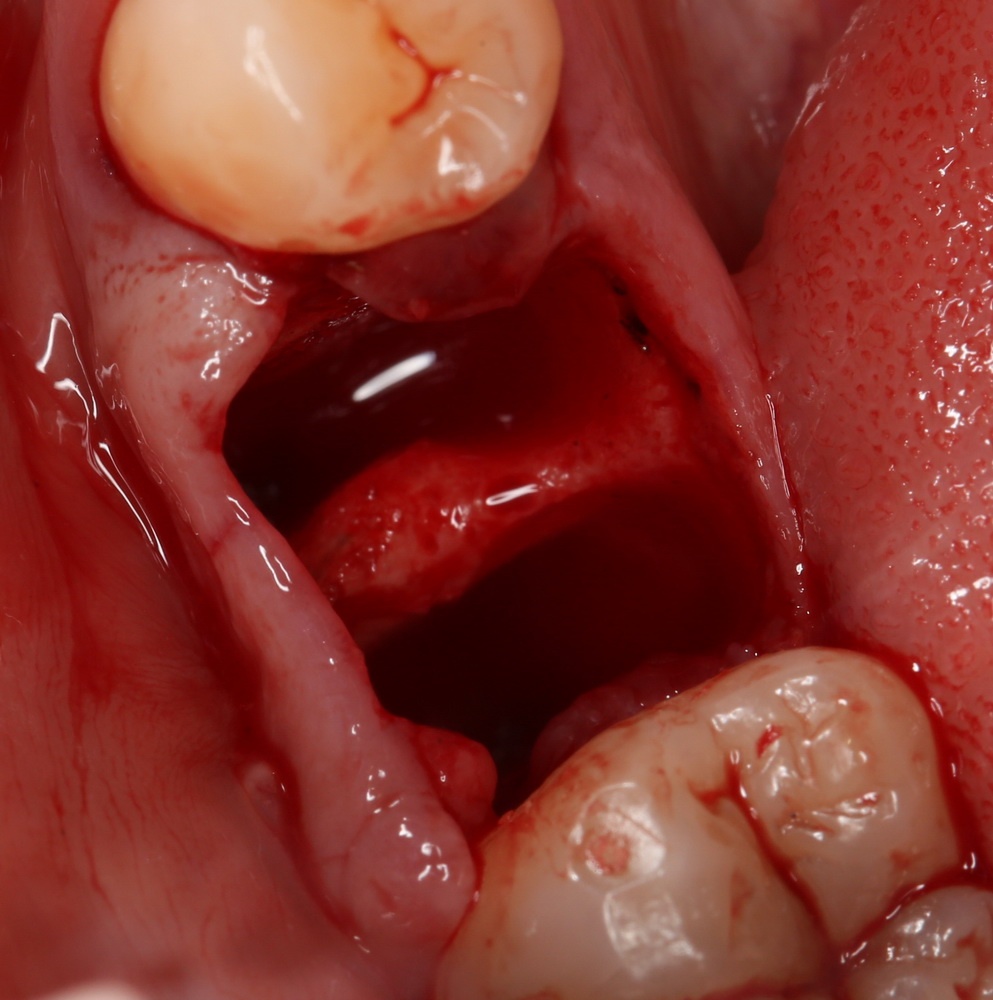

При удалении зуба повреждается мелкая сосудистая сеть, поэтому лунка начинает заполняться кровью. Кровотечение, в данном случае — один из видов защитной реакции организма. Формирующийся кровяной сгусток изолирует рану от внешней (агрессивной среды), а ток крови препятствует попаданию микробов и зубного налета в альвеолу. Кровь содержит ряд факторов, препятствующих развитию в лунке воспалительного процесса, обладает антисептическими и бактерицидными свойствами (в начале прошлого века, в доантибиотиковую эру, был разработан способ перевязки ран «кровяными» повязками, который очень хорошо зарекомендовал себя в военное время).

Поэтому, кровоточащая лунка зуба — это совершенно нормально. Причем, незначительное луночковое кровотечение может продолжаться длительное время — несколько часов, а то и сутки. Ничего страшного в этом нет. Я бы больше беспокоился, если бы лунка не кровоточила бы вообще. Как показывает практика, кровоточащие лунки легче и быстрее заживают.